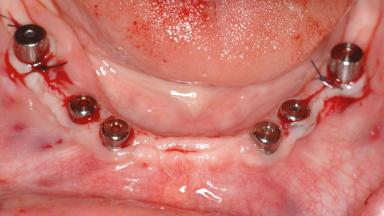

Le Fort I Interpositional Graft and Mandibular Sandwich Osteotomy for Maxillofacial Rehabilitation after Severe Periodontitis

A 47-year-old woman who had suffered from aggressive periodontitis requiring a number of periodontal interventions over more than 10 years was referred by her general dental practitioner and periodontologist for bone augmentation and implant therapy. Her failing dentition had already been scheduled for extraction. The patient expressed a desire for implant-supported fixed restorations and esthetic improvement of her lower face. She had agreed to consult with a maxillofacial surgeon after the referring dentist had suggested bone augmentation. An initial examination by the maxillofacial surgeon revealed mobility of all residual teeth in a patient who was very unhappy with the function of her removable partial dentures. Due to periodontally migrated flaring teeth and loss of occlusal support, the vertical dimension of occlusion was dramatically reduced. The patient was displeased with her lower face because of deepened nasolabial, commissural, and supramental folds.

# of Implants 14

Type of Implants Two-Piece

Defining Characteristics Fully edentulous upper jaw to be rehabilitated with four or more implants

Modality Fixed hybrid bridge on 5+ implants

Bone Volume Deficient vertically or deficient vertically AND horizontally